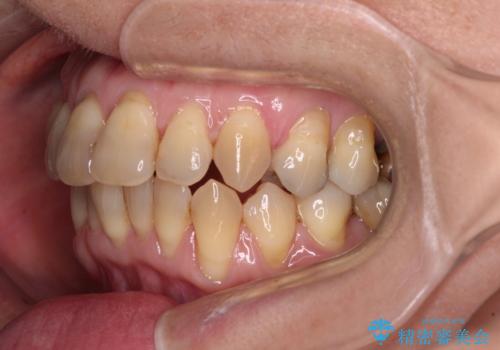

- 上下前歯のデコボコと、奥歯の銀歯を気にして来院された患者様です。

仕事柄あまり目立つ装置は付けることは避けたいとのことで、インビザラインによるマウスピース矯正を行うこととしました。

概ね歯列が整ったところで銀歯の全てをセラミッククラウンなどに置き換え、その後インビザラインを1セット使用して仕上げていくこととしました。